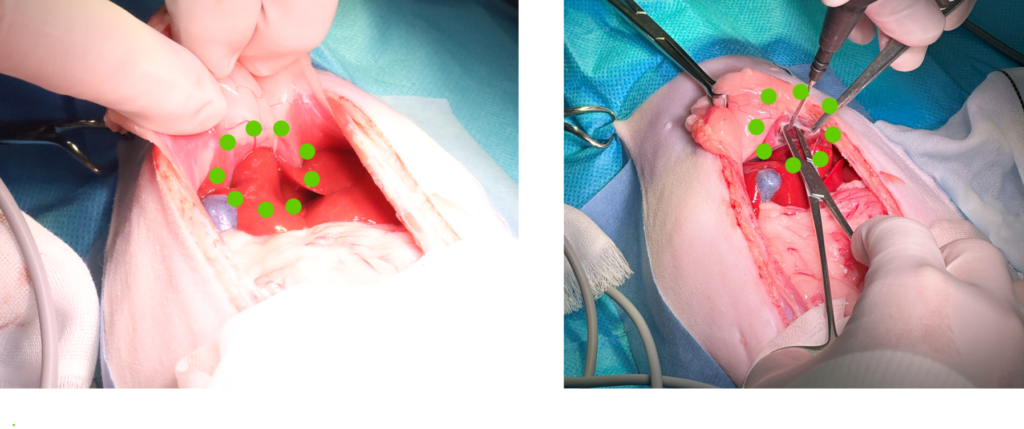

手術の様子

緑の点線が囲っている場所が横隔膜にあいた穴から肝臓が入り込んでいるところです。鉗子を使って周囲の膜をはがしていきます。